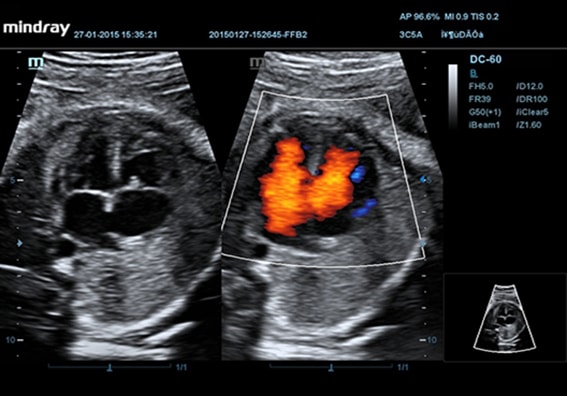

УЗИ-аппарат Mindray DC-55 - это передовое ультразвуковое оборудование, предназначенное для высококлассной диагностики пациентов. Благодаря своей высокой визуализации, он позволяет решать широкий спектр задач и обнаруживать даже наиболее сложные патологии тканей и органов в ранние стадии.

Mindray DC-55 обладает особым преимуществом - независимо от физической конституции пациента и плотности тканей, он обеспечивает высокое качество изображений без нежелательной зернистости. Это достигается благодаря использованию специальной технологии формирования мульти-луча и режима тканевого доплера с количественным анализом.

• Режимы сканирования B/M/Цветовой доплер CDI/Цветной M/Энергетический доплер

• PD/Направленный энергетический доплер Dir.PD

• HR Flow - режим отображения кровотока с высоким временным и пространственным разрешением для точной и однородной визуализации сосудов, в том числе самых мелких